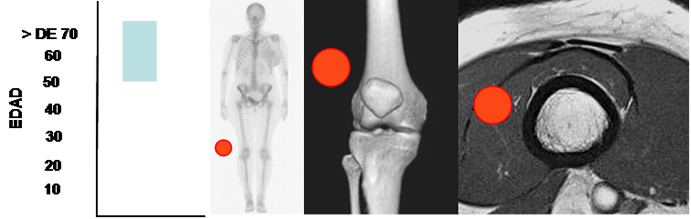

Son mas frecuentes entre la 5º y 7º décadas. (42).

Pueden ser solitarios o múltiples. Los superficiales abundan en la espalda, el cuello y la parte proximal de las extremidades (Hombro). Los profundo aparecen en las extremidades inferiores y puede ser intra o intermuscular. (9, 36, 42). (Fig 157).

Fig 157. Lipoma.

Mayor frecuencia entre la 5º y 7º década. Lesión de tejidos blandos con predominio en extremidades, espalda y hombros.